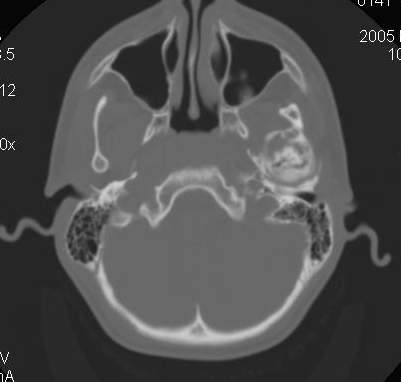

Пациент В., 13 лет. Диагноз: Костный анкилоз левого височно-нижнечелюстного сустава (ВНЧС), левосторонняя микрогения. Болеет с 2-х летнего возраста. Возможная причина развития анкилоза – воспалительный процесс (в первые 1,5 года жизни часто болел простудными заболеваниями, травму родители отрицают). В 3 и 5 лет проводилась редрессация – безуспешно.Прилагаются: ортопантомограмма, кадры СКТ с 3Д реконструкцией. Вопросы: определение тактики лечения – вид и сроки реконструктивно-пластической операции (этапов операции), а именно – неоартропластики и устранения микрогении, медикаментозная терапия в до- и послеоперационный период, ортодонтическое лечение.